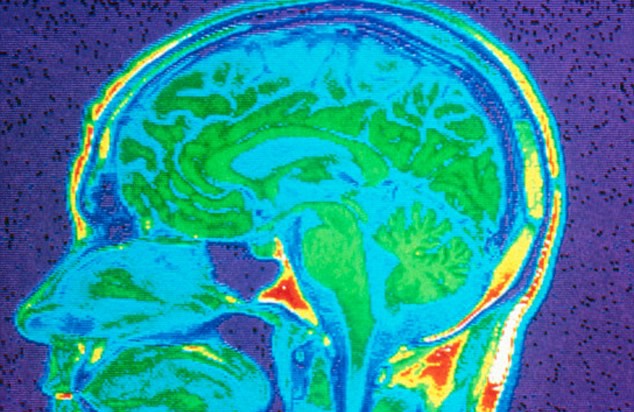

Based on the analysis of brain samples taken from the cadavers of both mentally ill and healthy people, they found that in  cases where the people had died by suicide, there was a lower-than-normal concentration of a gene known as SKA2. This gene is expressed in the prefrontal cortex of the brain – an area involved in inhibiting negative thoughts and controlling impulsive behavior.

depression_brainscanThis gene plays a part in the brain’s handling of stress hormones. If it isn’t functioning properly or lacking, stressful situations that would ordinarily be bearable can drive a person to contemplate or even attempt killing themselves. It was also found that the mutation not only reduced the levels of the gene, but also added chemicals called methyl groups to the SKA2 that was present.